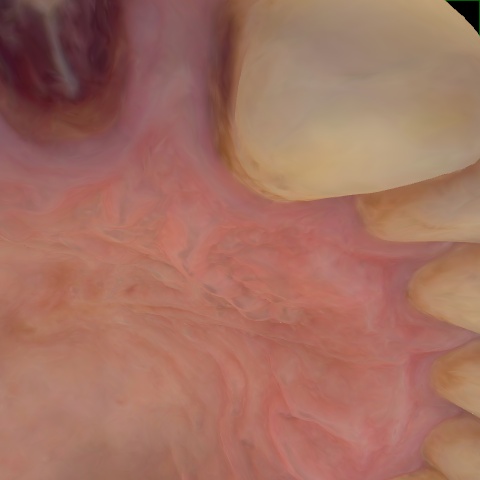

NHD36692

Annotated as "Good"

Original Image Rendering Image